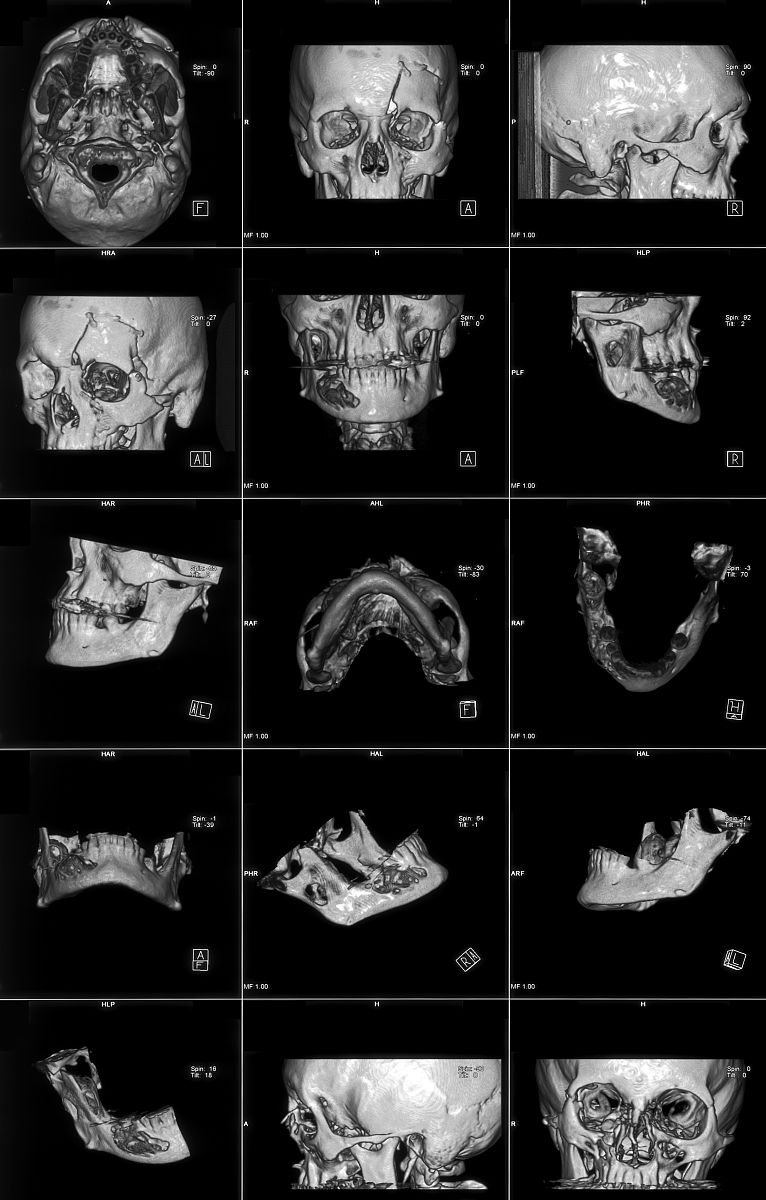

胚胎上颌隆起和下颌隆起来自胚胎的神经嵴和第一鳃弓。在胚胎发育的早期阶段,神经嵴会分化为不同的神经组织,其中包括上颌嵴和下颌嵴。这些嵴组织会进一步发展成为上颌和下颌的原始结构。

上颌隆起是来自上颌嵴的发展过程,它位于胚胎的头部前部,最终会形成上颌骨和上颌齿槽。

下颌隆起是来自下颌嵴的发展过程,它位于胚胎的头部下部,最终会形成下颌骨和下颌齿槽。

这些隆起的发展过程是复杂的,涉及多个生长因子、信号通路和细胞间相互作用的调控。它们的正常发育对于口腔和颌面的形成至关重要。